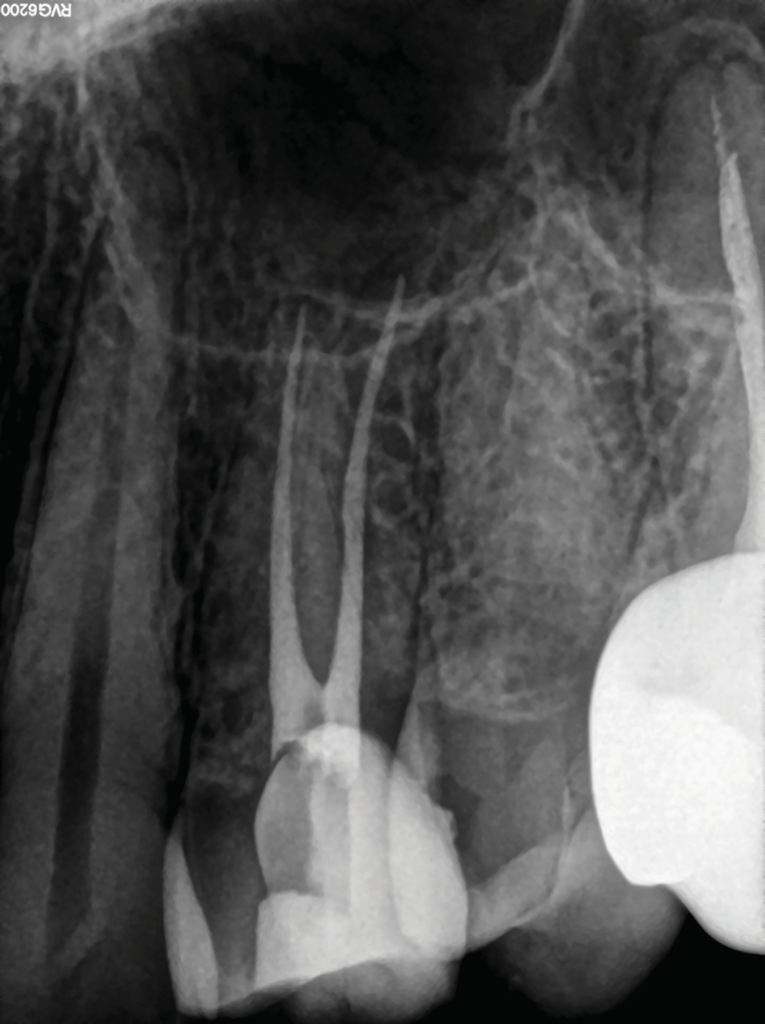

Figure 1 from Minimally invasive endodontics using a new singlefile rotary system Part 2 Single File Rotary Endodontics the metallurgy, design elements, and technique of propulsion (rotary/reciprocation) of rotary files have all undergone continual alteration,. recently, innovative metallurgy and reciprocating movement were combined to. Single File Rotary Endodontics.